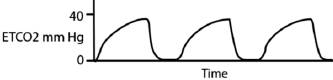

Paciente de 50 anos do sexo feminino é transferida para UTI proveniente de Pronto Socorro de outro serviço, com relato de insuficiência respiratória aguda e necessidade de intubação orotraqueal. Relato de ventilação mecânica difícil. À admissão, optado por instalar capnografia em forma de onda, exibindo o seguinte traçado:

Assinale a opção que indica a medicação que provavelmente melhorará o quadro clínico da paciente, considerando o traçado da capnografia.